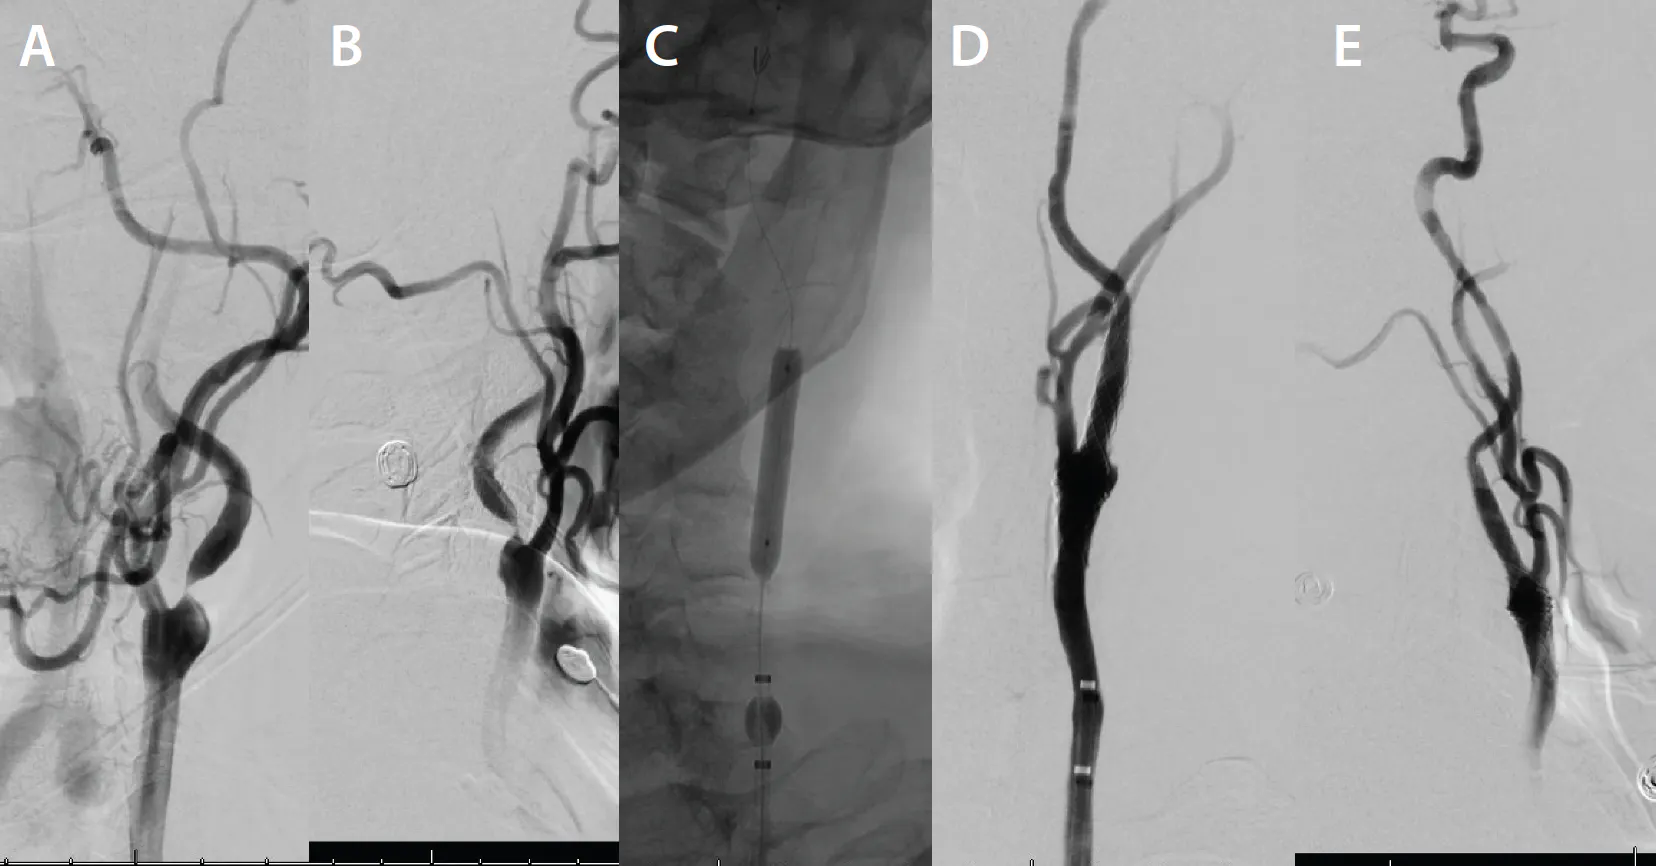

PROCEDURE

An 8-F right common femoral artery access was achieved, and the patient was systemically anticoagulated with heparin. A Bobby™ balloon guide catheter (BGC) (Terumo Neuro) was navigated over a 5-F Simmons Select catheter (Penumbra, Inc.) and a 0.035-inch Glidewire Advantage® guidewire (Terumo Interventional Systems) into the left CCA. Biplane cervical and cranial angiograms were then obtained. A 99% stenosis was present in the proximal left cervical ICA, with delayed filling of the intracranial vasculature and no evidence of occlusion (Figure 2A and 2B).

Figure 2. Prestent anteroposterior and lateral angiograms demonstrating near-complete occlusion of the proximal left cervical ICA (A, B). Inflated balloon across the stenotic lesion with BGC inflated for flow reversal and proximal protection (C). Anteroposterior and lateral angiograms after stent placement with significant improvement in caliber and flow (D, E).

The Bobby BGC was inflated, and the stopcock was opened to allow for back bleeding and flow reversal (Figure 2C). Under roadmap guidance, an Emboshield NAV6 embolic protection device (Abbott) was navigated across the stenotic lesion, into the distal cervical ICA, and deployed. This allowed for both proximal and distal embolic protection. With the NAV6 wire in place, a 5- X 30-mm Aviator balloon (Cordis) was navigated across the stenotic segment, inflated to nominal pressure, and maintained for 30 seconds. The balloon was then deflated and removed.

An 8- X 25-mm Roadsaver stent was then navigated across the stenotic region and deployed. Intermittent angiography was performed, demonstrating satisfactory stent deployment (Figure 2D and 2E). The NAV6 was then retrieved with a total filter time of 5 minutes. Final biplane cervical and cranial angiography was performed and showed brisk flow through the stent, with significant improvement in intracranial filling (Figure 3).

Figure 3. Prestent cranial angiogram showing sluggish and delayed intracranial flow (A). Poststent cranial angiogram demonstrating intracranial flow and significant improvement, with full opacification of the ACA and MCA and their arborizations (B).